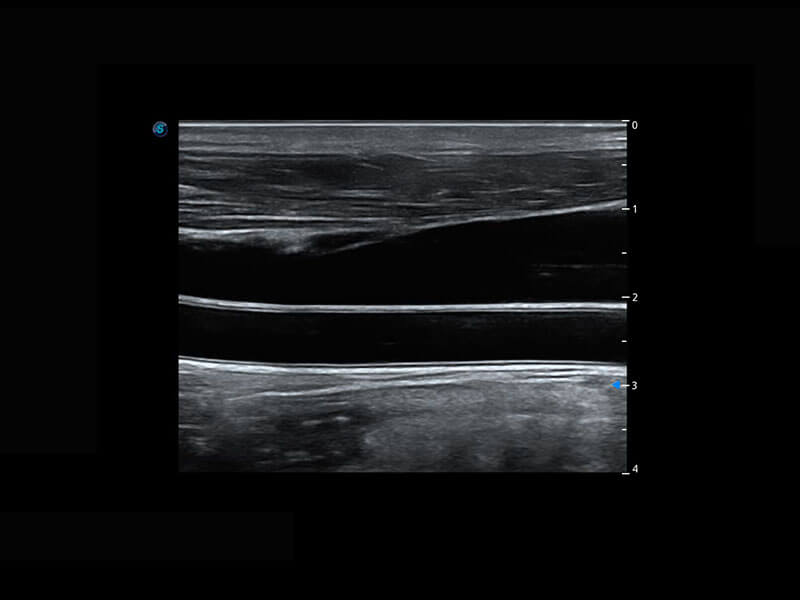

乳腺超声 / 新生儿

P60搭载宽频带线阵探头、宽景成像、弹性成像技术,为您提供乳腺应用方案。P60支持高频相控阵探头、线阵探头、腹部高频探头、腹部微凸探头等,丰富的探头群搭载敏感的彩色血流成像,适用于新生儿多种脏器检测要求,满足新生儿筛查需求。

• 新生儿脊髓圆锥